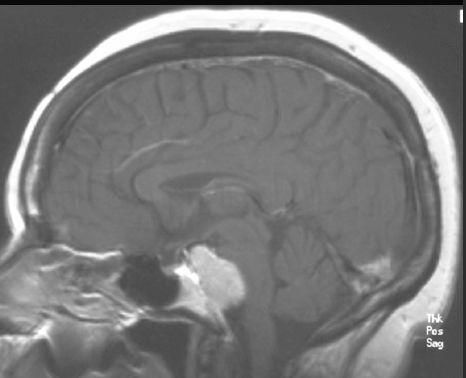

OPONIAK

MRI